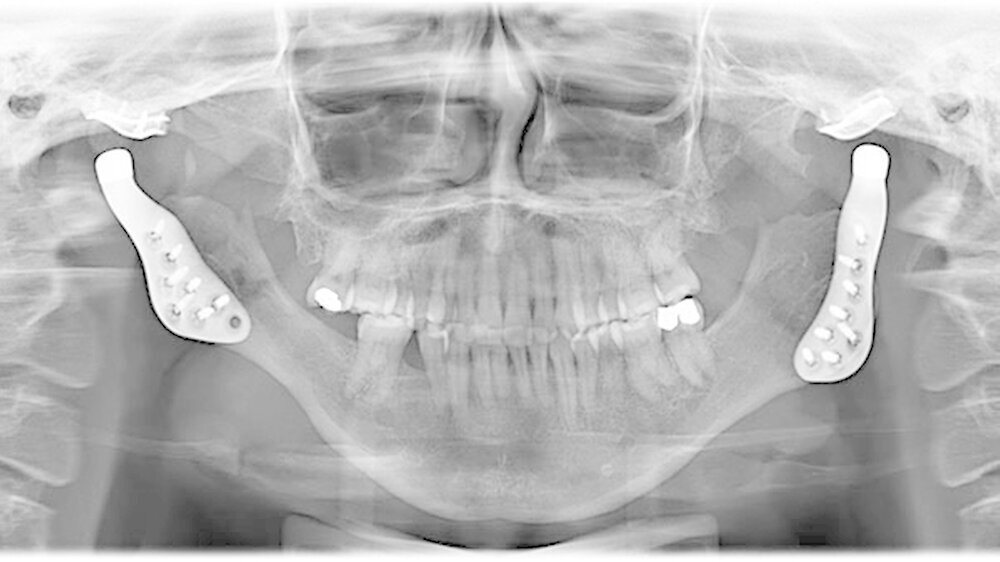

Das Bonner MKG-Chirurgenteam um Prof. Dr. Dr. Rudolf Reich diagnostizierte eine zunehmende Einschmelzung (Resorption) der Kiefergelenkfortsätze, wodurch die gesamte Abstützung des Unterkiefers am Schädel verloren gegangen war.

Da in diesen Fällen eine sichere Wiederherstellung der Abstützung des Unterkiefers mit eigenem Gewebe wie beispielsweise Knochen nicht möglich ist, weil eine erneute Einschmelzung droht, hat sich der Kiefergelenkersatz mit Endoprothesen bewährt.

Mit der virtuellen Planung, individuellen Kiefergelenkprothesen und einer zusätzlichen Rückpositionierung des Oberkiefers in die ursprüngliche Lage erfolgte dann die Operation. Alles erfolgte in einem Operationsgang. Die Bonner MKG-Chirurgen fertigten die Endoprothesen für die Frau individuell im CAD-/CAM-Verfahren an. Dafür wurden die Daten der Computertomografie des Schädels zugrunde gelegt.

Durch diese hoch anspruchsvollen Verfahren ließ sich annähernd die ursprüngliche Position des Unterkiefers vor der Einschmelzung wiederherstellen; in der gleichen Operation wurde die Position des Oberkiefers der jetzt idealen Stellung des Unterkiefers angepasst.